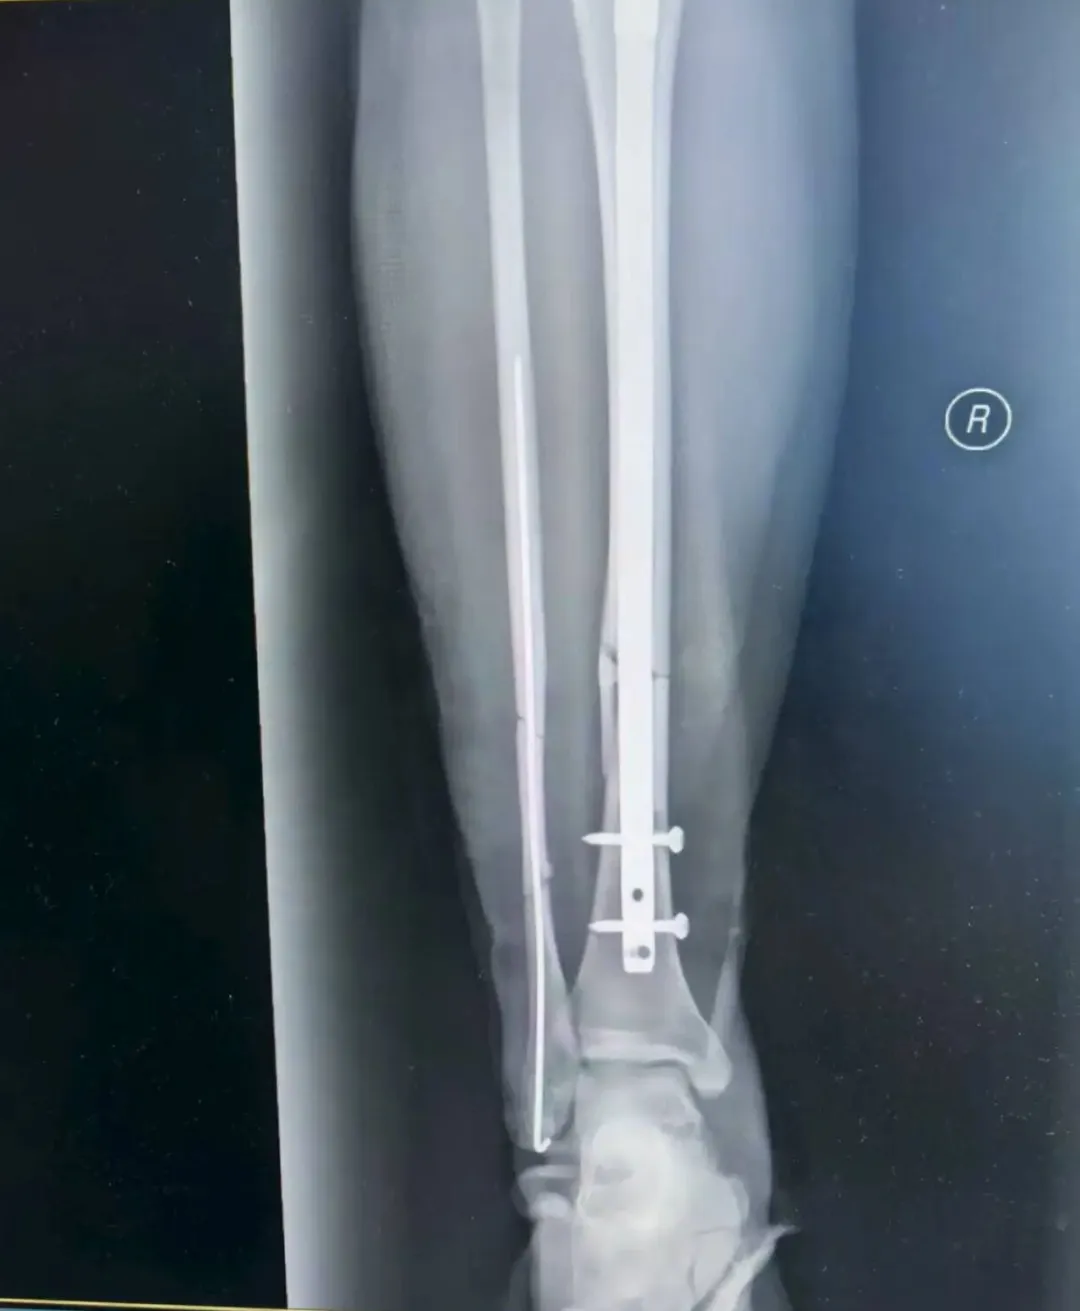

考虑到张女士是外地游客,不仅希望骨折能精准复位,还盼着创伤小、恢复快,不耽误后续返程与康复。董伟副主任医师结合影像学资料,综合考虑张女士的身体状况与个人需求,最终确定采用“胫腓骨骨折闭合复位+胫骨髓内钉内固定术+腓骨髓内针内固定术”,全程无需做大切口,通过微创方式实现骨折端精准对位,既能最大程度保护肿胀的软组织,又能显著提升术后恢复速度。

手术由董伟、孙毅珲共同完成,术中借助C臂机实时透视引导,小心翼翼地通过闭合复位技术调整骨折端位置,确保达到解剖复位标准;随后精准植入胫骨髓内钉与腓骨髓内针,完成固定。整个手术过程出血少,术后仅留下几个微小创口,最大程度减少了张女士的痛苦。

如今术后已经一周,张女士恢复情况远超预期:微创留下的针眼愈合良好,没有出现红肿、渗液等异常情况;主管医生孙毅珲每日都会到病房查看她的恢复情况,指导她完成床上肌肉训练——从踝泵运动到股四头肌收缩,张女士每个动作都做得认真,“孙医生每天都耐心教我怎么练,现在小腿不怎么肿了,也不怎么疼,能明显感觉到腿上的劲儿在慢慢回来”。